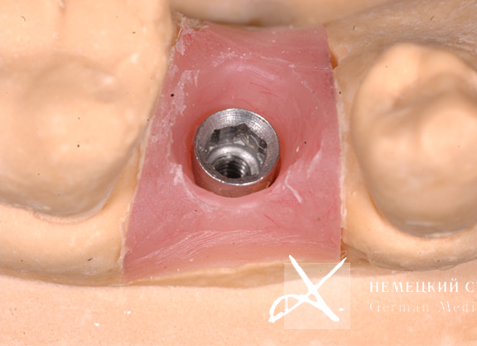

Учитывая тот факт, что диаметр имплантата практически всегда вынужденно меньше диаметра восстанавливаемого зуба в данной анатомической области, чтобы получить максимально эстетический и функциональный результат, было сделано:

- Поэтапное "выстраивание" десневого контура ("кратера прорезывания") с помощью индивидуально моделируемой диагностической промежуточной коронки и индивидуально построенной супраструктуры (абатмента), выполненной из золотосодержащего сплава.